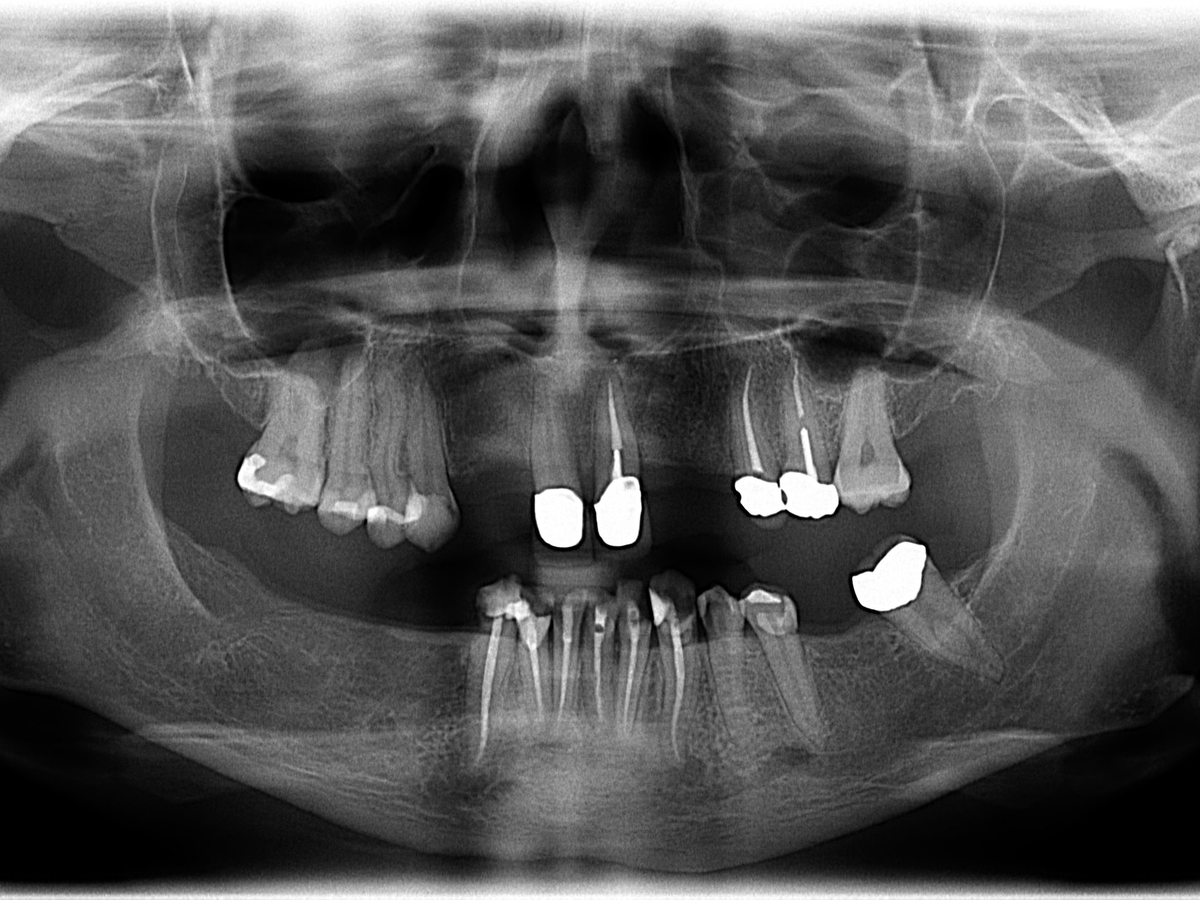

In my case, lack of care was not the only issue. I was born without several of my adult teeth. One of my teeth decided to grow sideways inside my jaw, which necessitated surgery to remove. My top front teeth are off-center as a result. I have soft enamel, periodontal disease, and bone loss in my jaw. Because of the high costs of care, whenever I would develop a problem, the cheapest solution was to just pull the tooth. Not ideal, but when you’re in an extreme amount of pain from an abscess bad enough to stop a human heart, you’ll do what you must do to make it stop.

I have sixteen teeth remaining. I am now unable to chew properly and have almost stopped eating solid food entirely. I am rapidly losing weight, and my mouth hurts all the time, every day. I wake up in pain and go to bed in pain. Eating hurts every single time. Sometimes my gums are so inflamed I can’t even drink or swallow. I struggle with multiple infections a year, and it’s almost certain my teeth are the source of my chronic migraines.

If you made it this far, bless you. I will continue to upload more information as I obtain it—for one thing, I have the estimates for care by local dentists, I have photos, x-rays, and coming soon: video. I will also interview my friends so you can get an idea of who I am as an individual, in the interest of full transparency. If this fundraiser is successful, I will then use it to document my dental journey and provide receipts as the work is completed.